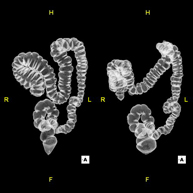

- Virtual colonoscopy

Virtual colonoscopy is a non-invasive technique that allows three-dimensional and two-dimensional visualisation of the large intestine or colon by taking sequential images captured with a state-of-the-art MDCT scanner. The quality of the images allows virtual navigation through the rectum and colon thanks to processing on specialised workstations. Preparation for the test consists of following a low-fibre diet for three days before the test (to cleanse the colon and rectum) and ingesting an iodinated oral contrast agent the day before the test (to mark the stool so that it can be correctly distinguished from any colonic lesions). Unlike fibrocolonoscopy, no sedation or bowel preparation is required. The test is performed in the CT room, where air is blown through a small flexible tube to distend the colon.